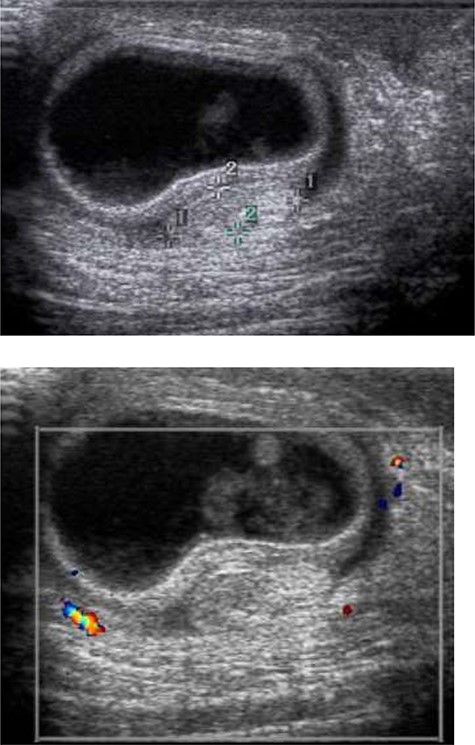

While awaiting transfer to a hospital with pediatric surgical capabilities, intravenous fluid resuscitation was initiated. Ultrasound of the scrotum was performed assessing gray scale appearance and color Doppler flow. The left testis demonstrates a homogenous echotexture and measured ~1.5 × 0.6 × 1.3 cm in the longitudinal, anterior/posterior and transverse dimension. Vascular flow is demonstrated on color Doppler images with arterial and venous waveforms. The right testis and inguinal region demonstrated a right inguinal hernia containing a loop of bowel within the right scrotum with echogenic bowel contents. A hyperechoic ovoid structured, favored to represent the right testicle, is seen measuring ~1.0 × 1.0 × 0.4 cm. There is no sonographic evidence of vascular flow to the right testicle (Fig. 2). This combination of findings is favored to represent testicular vascular compromise and probably infarction secondary to spermatic cord compression from the right inguinal hernia. There is additional concern that this right inguinal hernia is incarcerated. The outside hospital was updated regarding our ultrasound findings, with pediatric general surgery and urology awaiting arrival of the patient for immediate surgical intervention at ~18 hours post symptom onset. The patient’s hospital course was unremarkable, his testicle and all bowel were preserved. He was transferred to the intensive care unit after surgery on high-flow and was discharged home 3-days later. At his 1-month follow-up appointment, the patient is doing well, and his mother denies any concerns.

Ultrasound of the scrotum was performed assessing gray scale appearance and color Doppler flow. The right testis and inguinal region demonstrates a right inguinal hernia containing a loop of bowel within the right scrotum with echogenic bowel contents. A hyperechoic ovoid structured, favored to represent the right testicle, is seen measuring ~1.0 × 1.0 × 0.4 cm. There is no sonographic evidence of vascular flow with the right testicle.